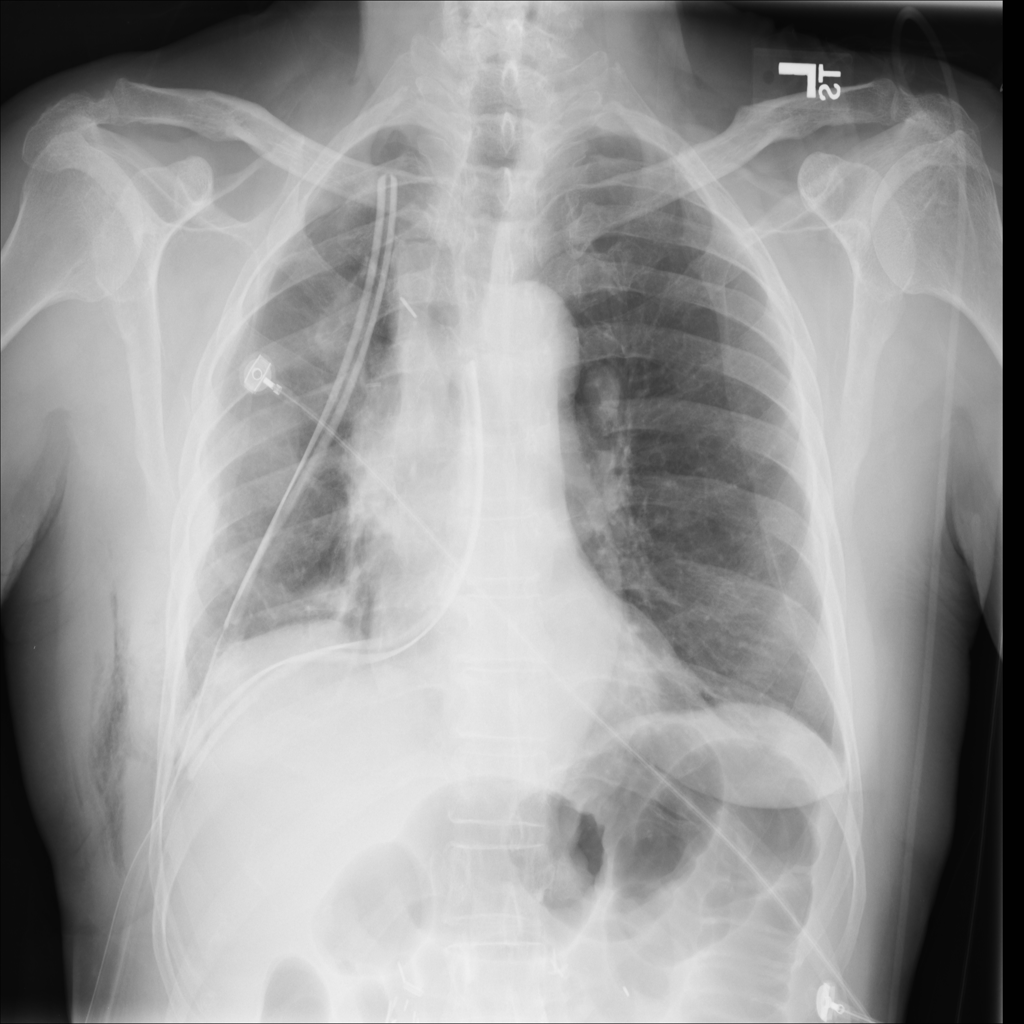

PAT-4639 · IMG-012Pneumothorax

PAT-4639 · IMG-012

AP